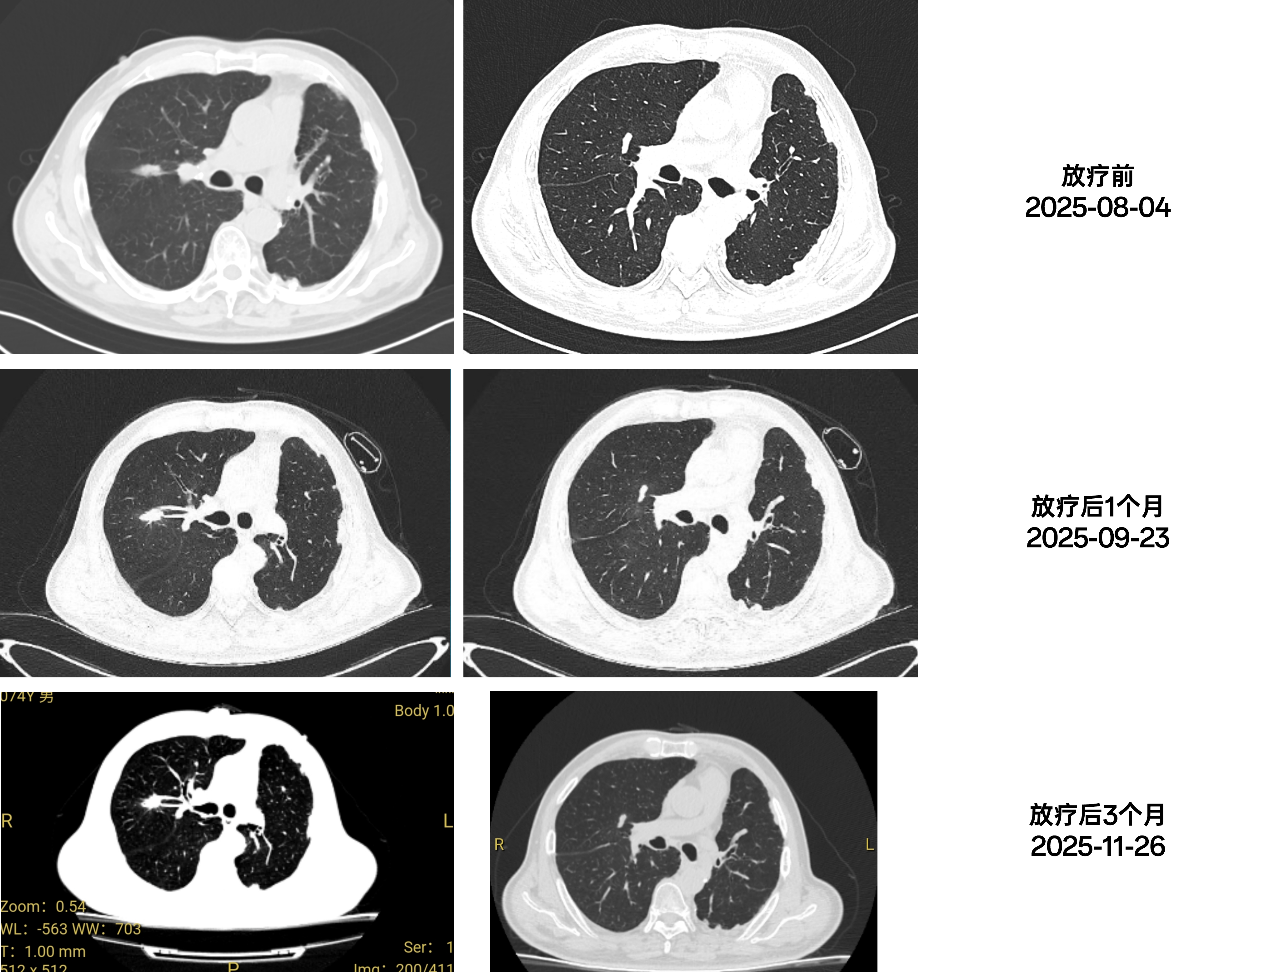

2025-08-06至2025-08-26,排除放疗禁忌后,行姑息性放疗,具体:肺上叶、中叶转移灶:60Gy/15FX,4Gy/FX,放疗期间联合甘氨双唑钠放疗增敏,予以雾化吸入止咳化痰,保肝等对症治疗。

2025-09-23,放疗后1月,复查胸部CT:左肺术后改变,请结合临床病史。左肺胸膜下多发结节、钙化灶。右肺上叶结节,对比前片未见明显改变。右肺上叶多发磨玻璃结节。右肺中叶结节,对比前片略小,肺气肿、肺大泡。左侧胸膜及肋骨改变,主动脉及冠状动脉硬化性改变。

2025-11-26,放疗后3月,复查胸部CT:左肺术后改变,请结合临床病史。左肺胸膜下多发结节、钙化灶。右肺上叶结节,右肺中叶结节对比前片未见明显改变。肺气肿、肺大泡。左侧胸膜及肋骨改变,主动脉及冠状动脉硬化性改变。